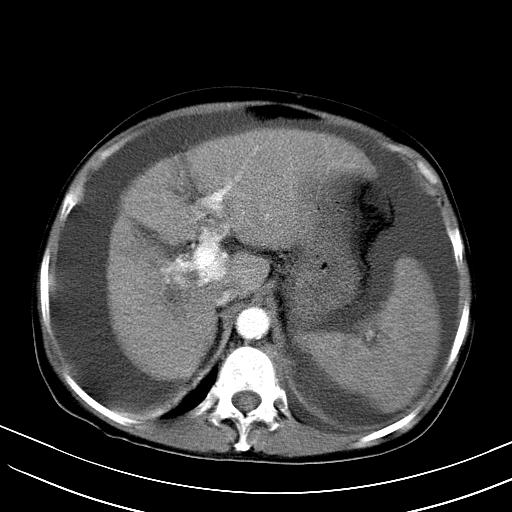

1)肝右叶肝癌并肝动静脉漏。2)肝硬化,腹水。3)胆囊炎。

肝右叶肝癌并动静脉漏,肝硬化,腹水。

1)肝右叶肝癌并肝动静脉漏 门v右支瘤栓伴海绵样变。2)肝硬化,脾大 腹水。3)胆囊炎。门v高压.

1)肝右叶肝癌并肝动静脉漏。2)肝硬化,腹水。3)胆囊炎。 4,脾大,脾囊肿

右叶肝癌并肝动静脉漏(动脉期肝动脉及门静脉内均可见造影剂),肝硬化,腹水。(胆囊壁水肿)